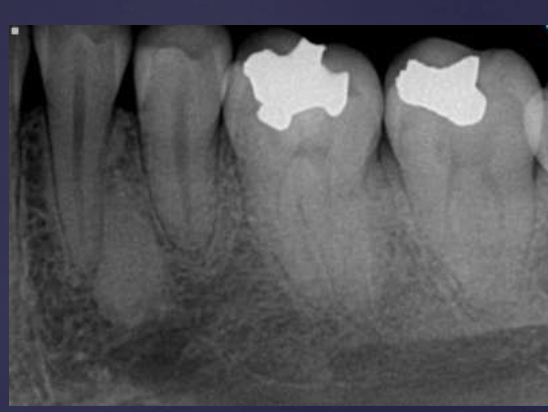

T/F: you can see B/L expansion in this radiograph

false, since this PAN is a superimposed image- you cannot tell